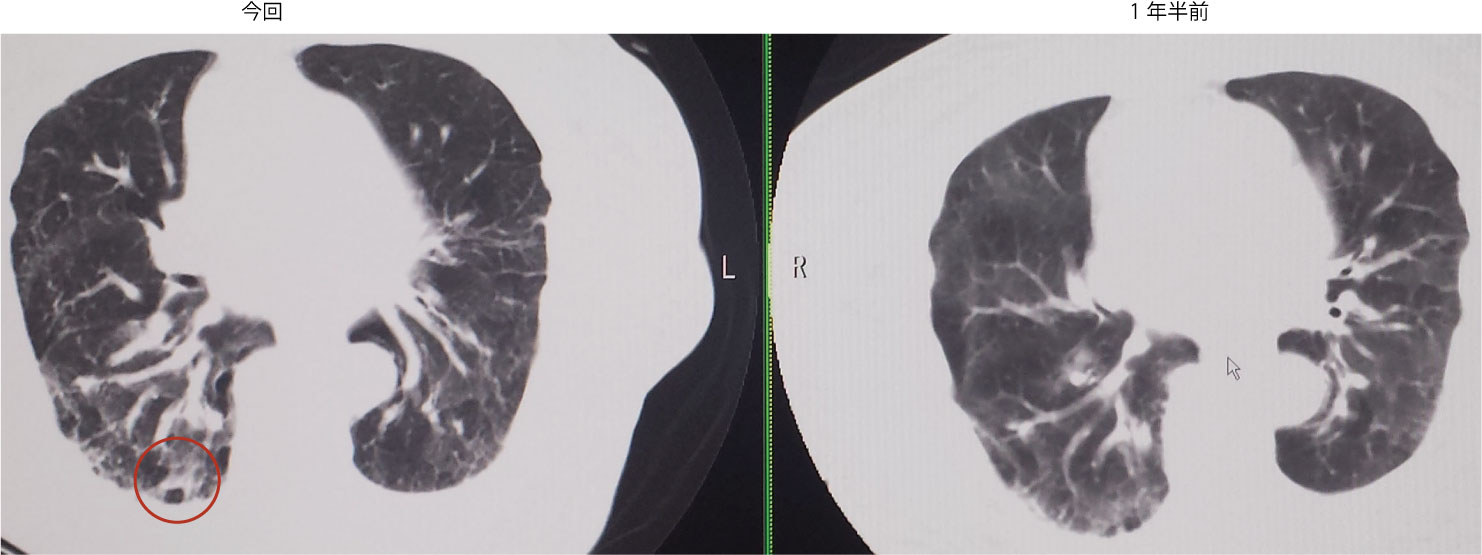

・Day5:37.7℃。CRP 7.26, WBC 7030, 好中球81.5%。胸部CT:加齢性線維化+右誤嚥性肺炎疑い。腹部CT:熱源無し。クラビット点滴追加。